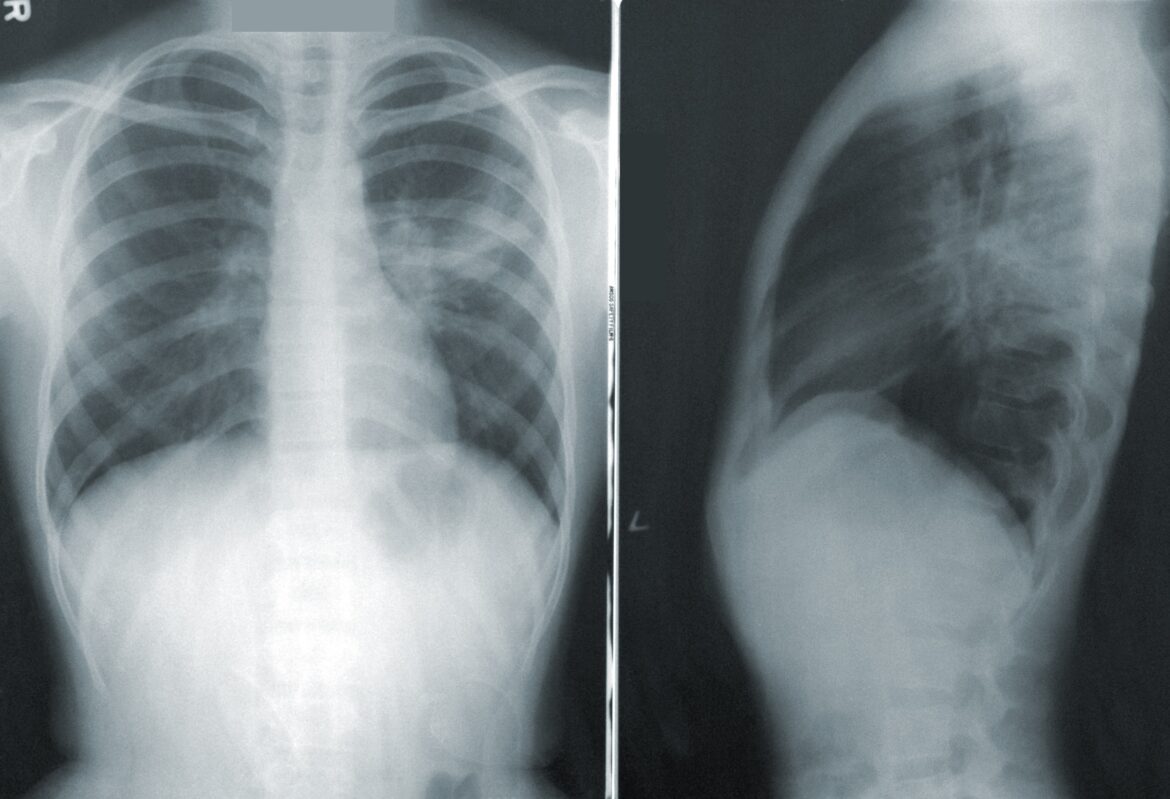

Early detection is critical for successful treatment. AI systems can identify suspicious abnormalities more accurately than manual methods by looking at images from CT scans, PET scans, MRIs, ultrasounds, and radiographs. The AI can also detect changes over time that may be difficult for a human eye to spot on a single image. AI-powered systems like the Voxel-Man Atlas help doctors determine when an abnormality should be looked into more closely or deemed likely benign and not requiring further workup evaluation.